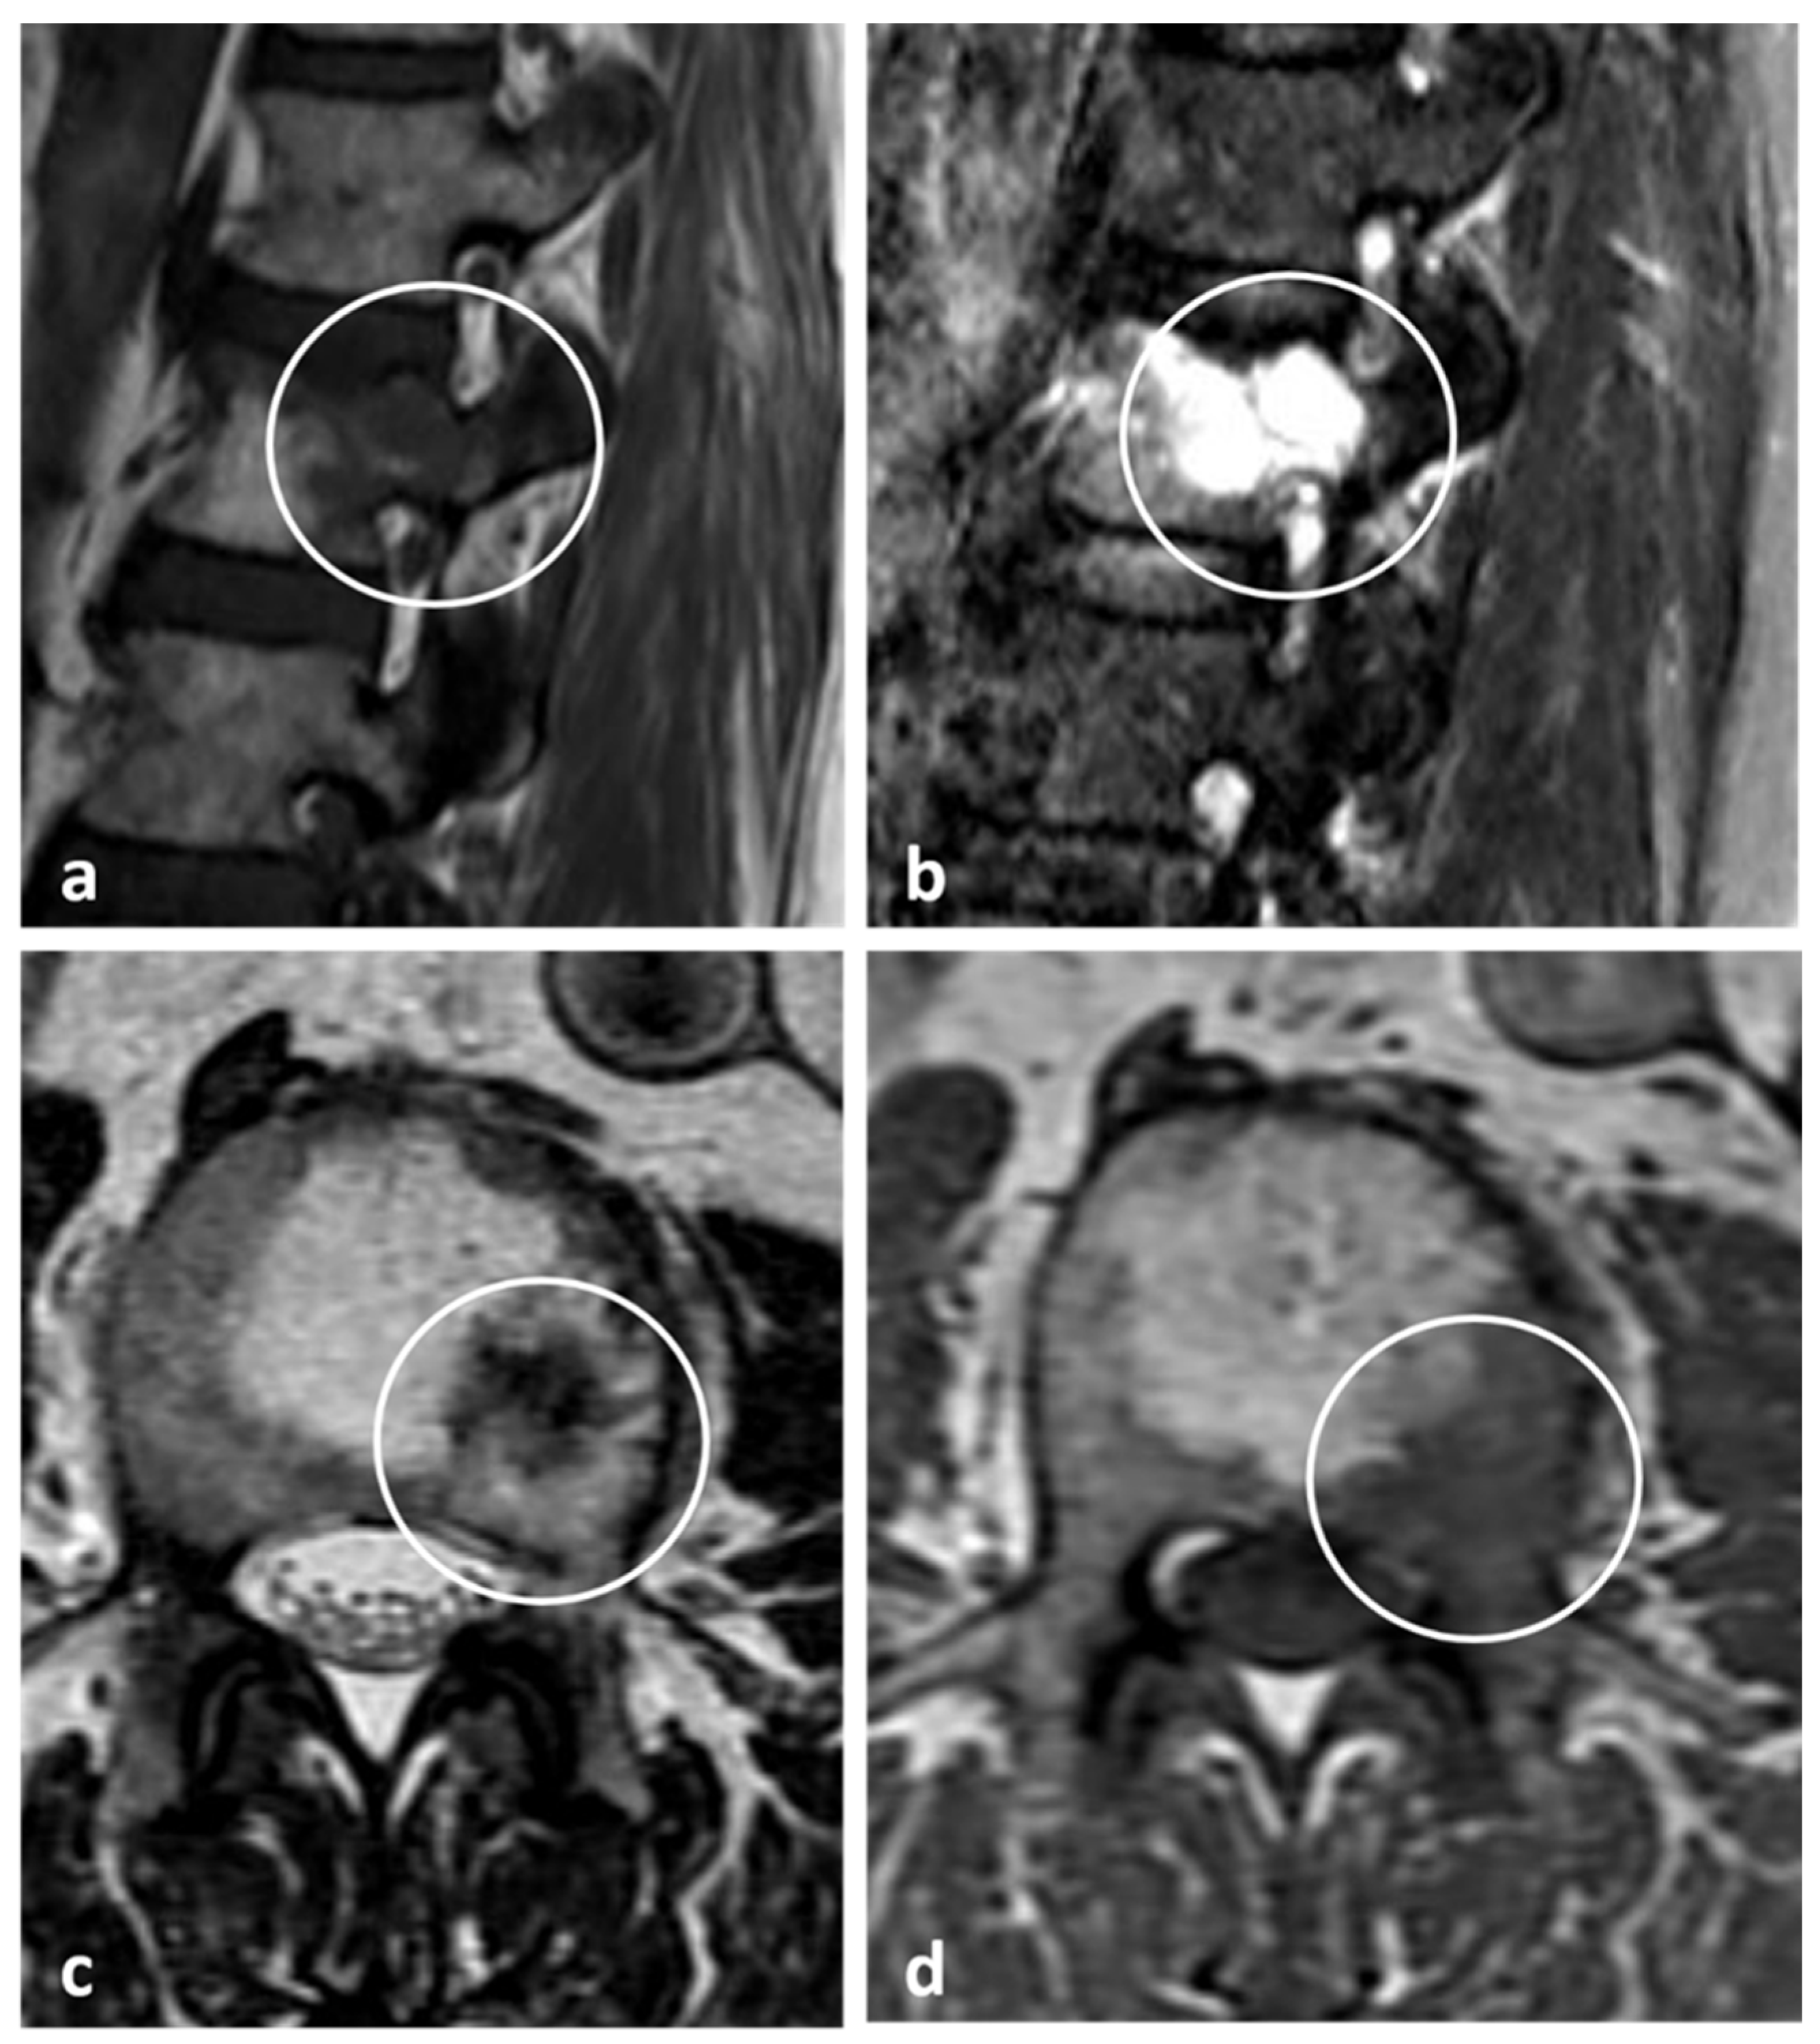

3.11. Giant Cell Tumour (Benign Variant)

| Giant cell tumour | Mixed cystic and solid expansile lesions, with thin peripheral bony shell. ‘Soap bubble’ appearance. | Secondary ABC change is common, with fluid—fluid levels. Intermediate to low signal intensity on both T1 and T2. Enhancing soft tissue component. |